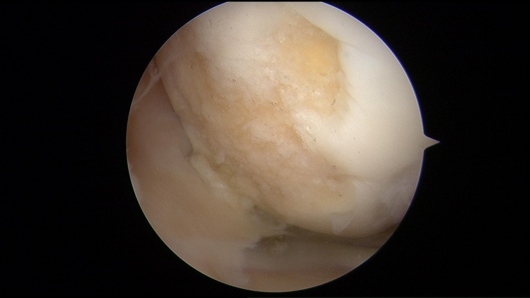

Además de la cirugía de reemplazo articular, me especializo en procedimientos de preservación articular y artroscopia de cadera y rodilla, buscando siempre retrasar o evitar la cirugía de reemplazo articular cuando es posible.

- Artroscopia

- Osteoartritis

- Desgarre de meniscos